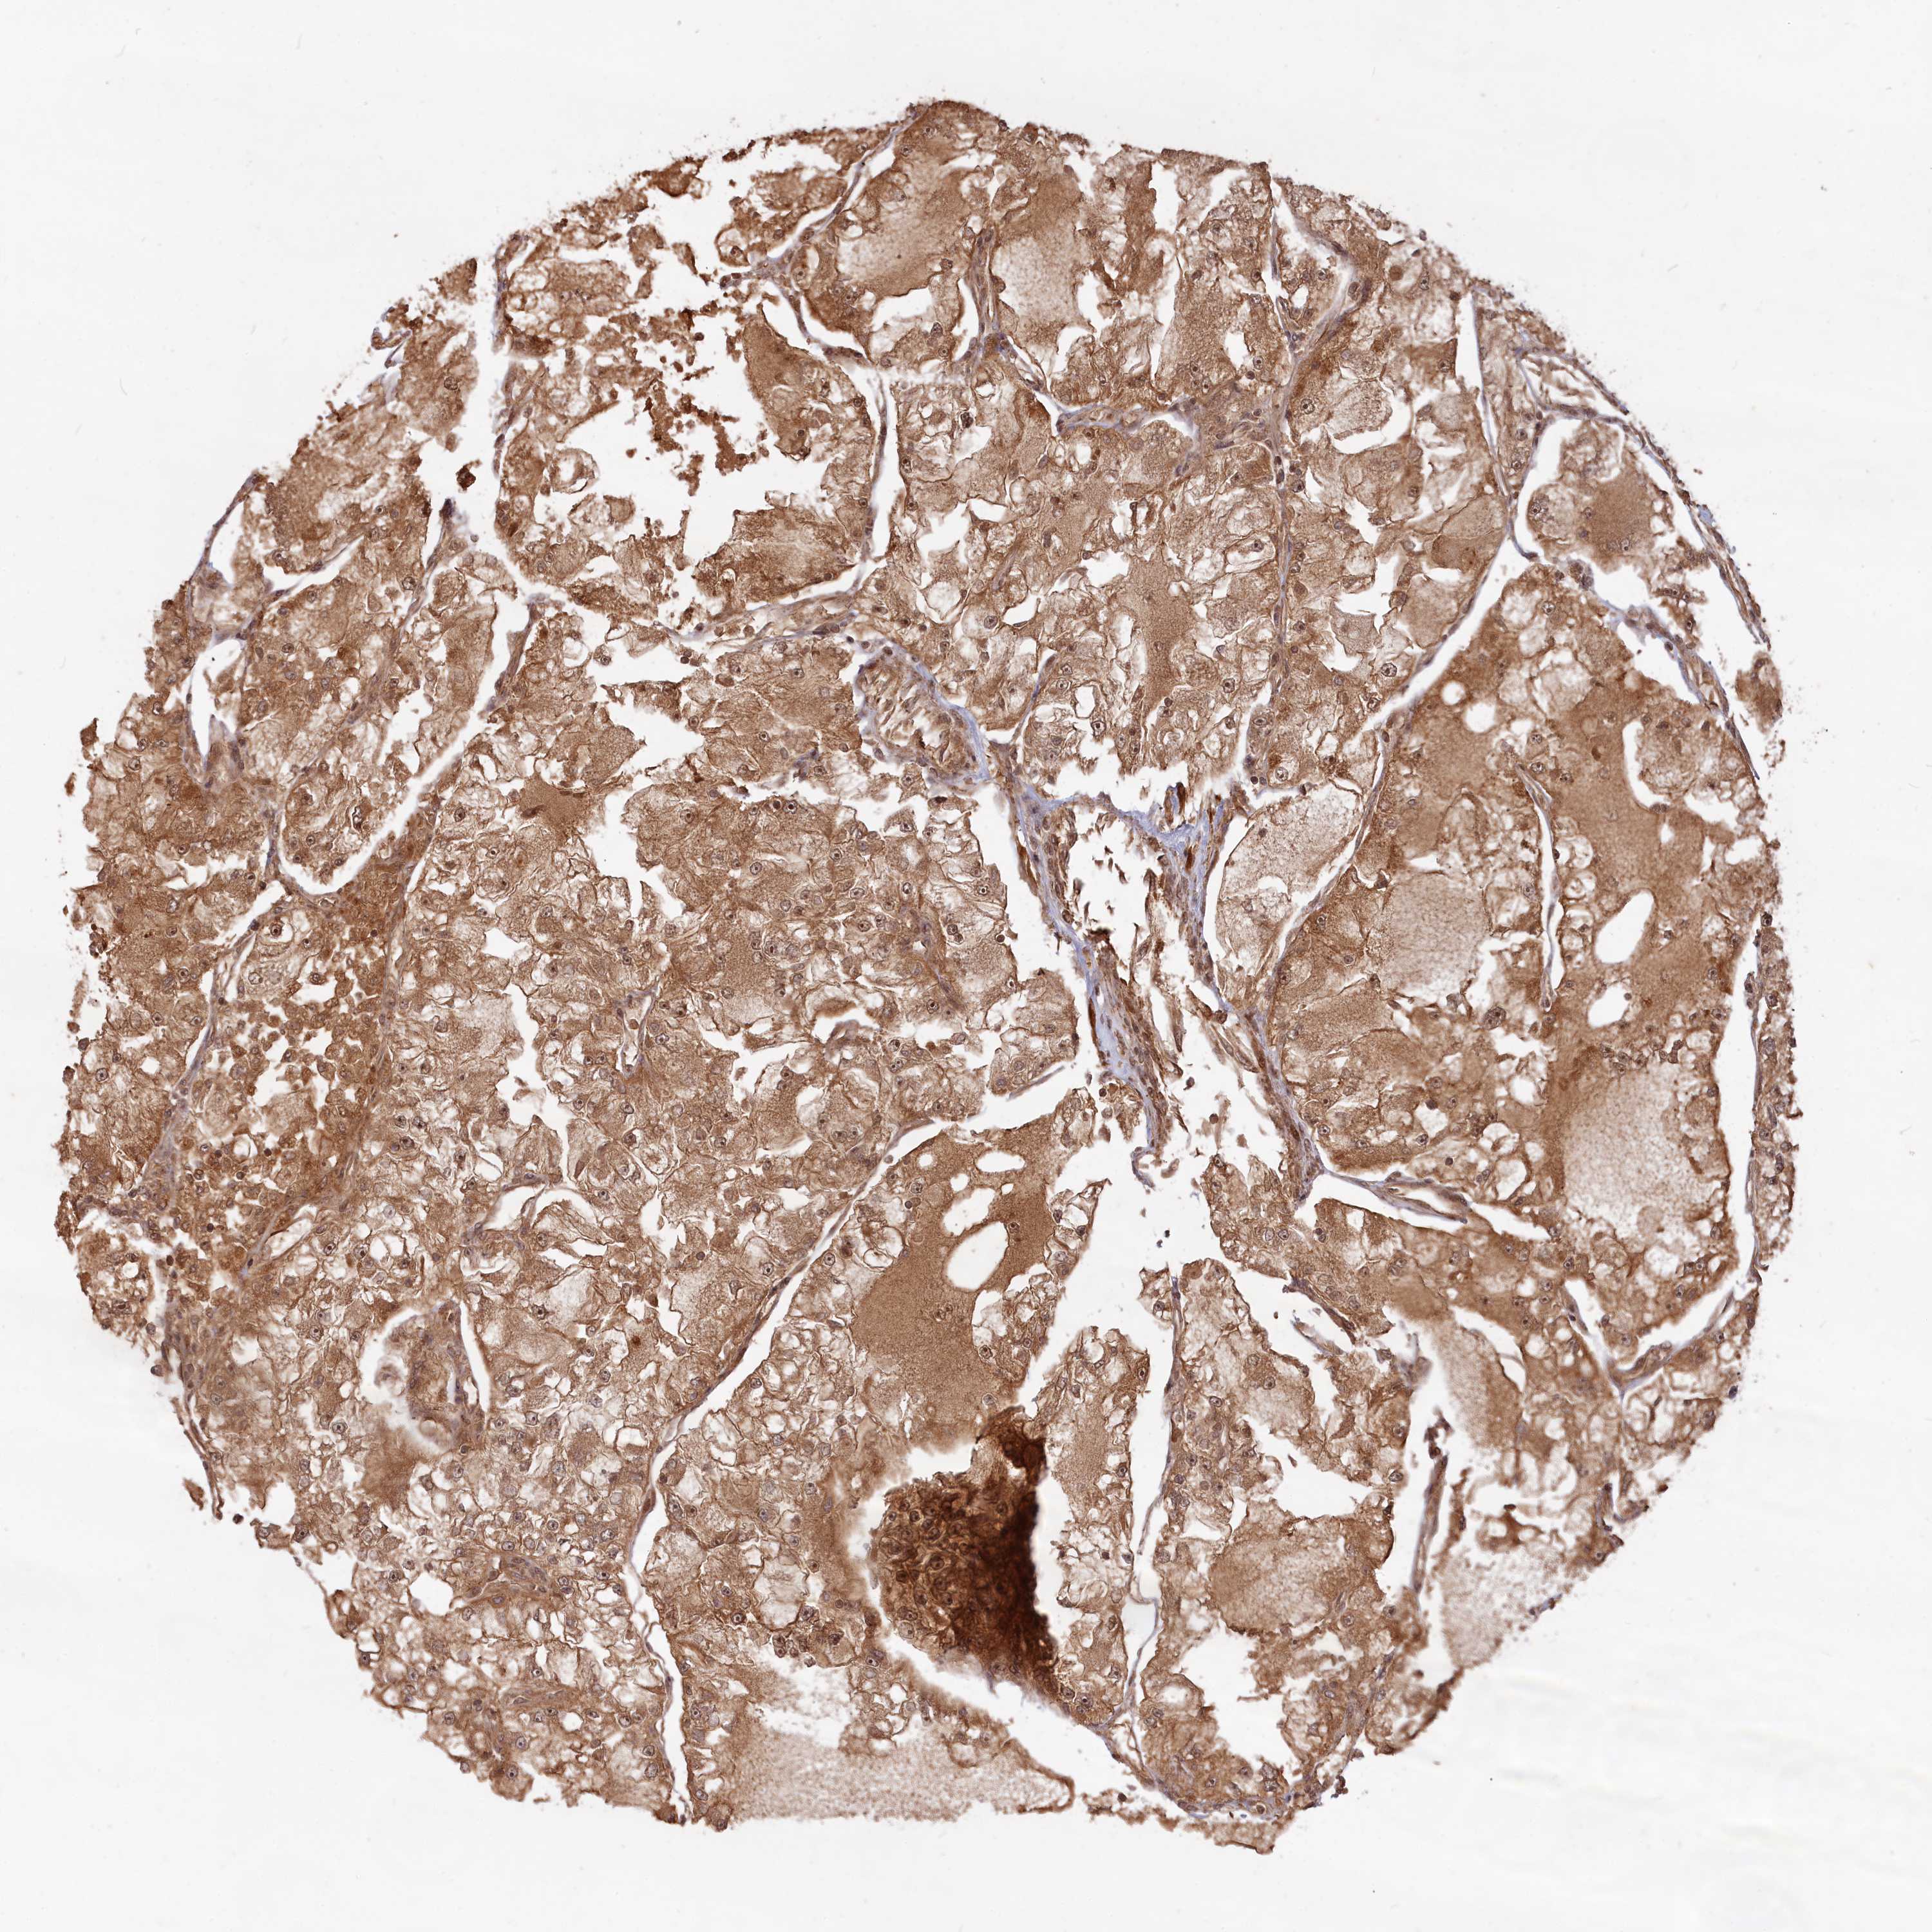

KIDNEY RENAL PAPILLARY CELL CARCINOMA (TCGA) - Interactive survival scatter ploti

The Survival Scatter plot shows the clinical status (i.e. dead or alive) for all individuals in the patient cohort, based on the same data that underlies the corresponding Kaplan-Meier plots. Patients that are alive at last time for follow-up are shown in blue and patients who have died during the study are shown in red.

The x-axis shows the expression levels (FPKM) of the investigated gene in the tumor tissue at the time of diagnosis. The y-axis shows the follow-up time after diagnosis (years). Both axes are complimented with kernel density curves demonstrating the data density over the axes. The top density plot shows the expression levels (FPKM) distribution among dead (red) and alive patients (blue). The right density plot shows the data density of the survived years of dead patients with high and low expression levels respectively, stratified using the cutoff indicated by the vertical dashed line through the Survival Scatter plot. This cutoff is automatically defined based on the FPKM cutoff that minimizes the p-score. The cutoff can be changed by dragging the vertical line or by entering a cutoff value in the square labeled "Current cut-off".

Under the Survival Scatter plot the p-score landscape (black curve; left axis) is shown together with dead median separation (red curve; right axis). Dead median separation is the difference in median mRNA expression between patients who have died with high and low expression, respectively. It is calculated as follows: median FPKM expression of dead patients with high expression - median FPKM expression of dead patients with low expression. This is intended to aid the user in visually exploring custom cutoffs and the associated p-scores and dead median separation.

Individual patient data is displayed and can be filtered by clicking on one or more of the category buttons on the top of the page. Categories describing expression level and patient information include: high, low, alive, dead, female, male and tumor stages. The scale of the x-axis can be toggled between linear and log-scale by clicking on the "x log" button. Mouse-over function shows TCGA ID, patient information and mRNA expression (FPKM) for each patient.

& Survival analysisi

Kaplan-Meier plots summarize results from analysis of correlation between mRNA expression level and patient survival. Patients were divided based on level of expression into one of the two groups "low" (under cut off) or "high" (over cut off). X-axis shows time for survival (years) and y-axis shows the probability of survival, where 1.0 corresponds to 100 percent.

CCDC174 is not prognostic in Kidney Renal Papillary Cell Carcinoma (TCGA)